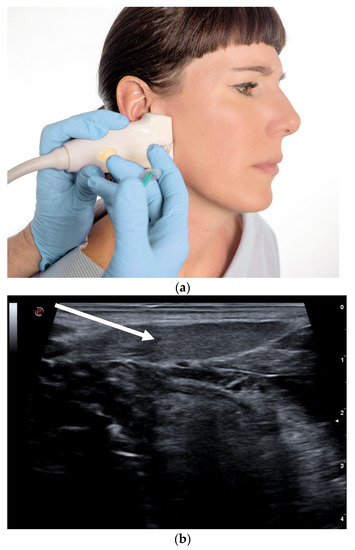

- Flexion of the toes:This second form usually causes more discomfort to the patients, as it induces involuntary movements in the toes, in particular the small ones, but also the big toes. It occurs frequently as exercise-induced dystonia. Here, a distinction has to be made whether only one of the two or both toe flexing muscles are involved. The short flexor is found in the sole of the foot, the long flexor in the lower calf. Here too the injection into the muscle is performed under ultrasonic guidance (see Figure 4).